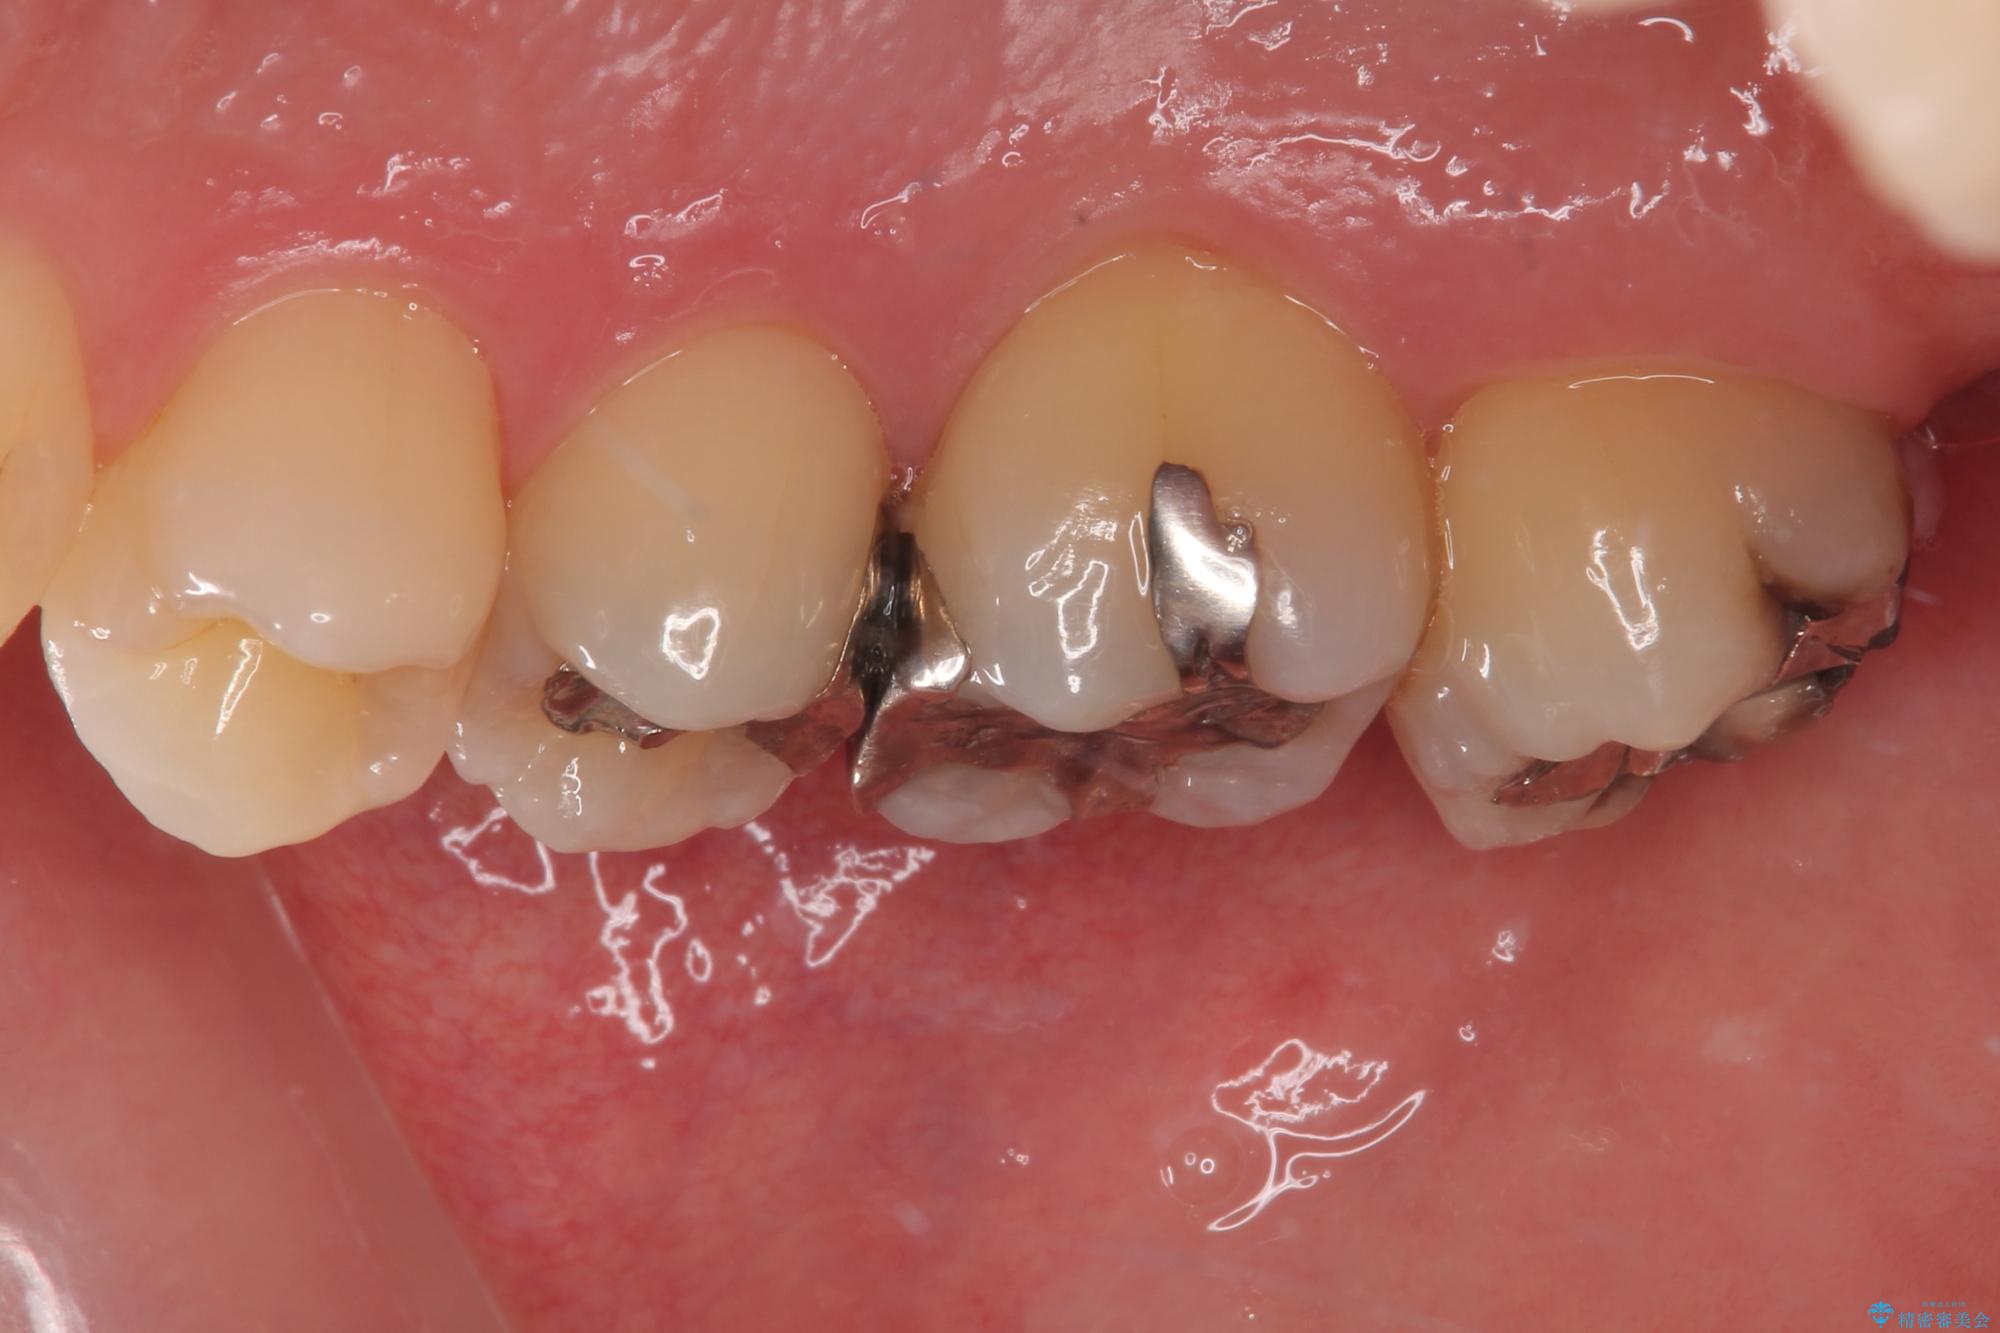

- 元々むし歯があったものの、処置が困難とのことでしたが、矯正治療を終えたので処置をしたいとのことで来院された患者様です。

左右ともに最後臼歯が頬側に顕著に突出しており、むし歯になってしまったことが想像されました。

矯正治療により処置が可能な位置に歯が移動したため、オールセラミッククラウンにて補綴治療を行うこととしました。

歯列が移動したとはいえ、左右ともに後方傾斜しており、むし歯の除去、形成(形を整える)、型取りの全てが非常に困難な処置となりました。